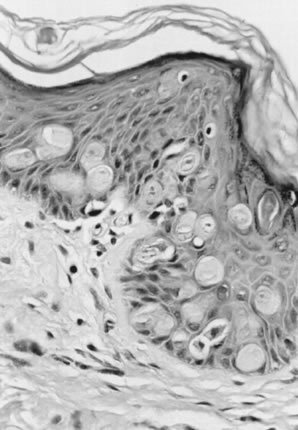

In normal squamous epithelium, the basal cells divide and thereafter differentiate in a fixed postmitotic fashion. As maturation occurs, cytoplasm is acquired, granules of prekeratin are formed, and the cellular outline and nucleus eventually are lost in the superficial keratin layer. In VIN lesions, the epithelial cells continue to exhibit large nuclei with nuclear hyperchromasia as they progress upward. These cells are atypical. Mitotic figures are found elsewhere than in the basal layer and are often atypical in appearance. Multinucleation implies impairment of the cell division mechanism. Nuclear pleomorphism, hyperchromasia, and loss of maturation are evidence of abnormal development (Figs. 3 and 4). Finally, the rate of epithelial cell division and the number of cells undergoing cell division may be increased, resulting in an increased density of the cell population.

Fig. 4. Vulvar intraepithelial neoplasia (VIN) 3 (severe dysplasia/carcinoma in situ ), warty type. Atypical cells extend throughout the full thickness of the epithelium. There is nuclear pleomorphism with koilocytes near the surface.

Warty (condylomatous) type: These resemble condyloma acuminatum (Fig. 1) with koilocytosis, hyperkeratosis, and dyskeratosis (Fig. 4)